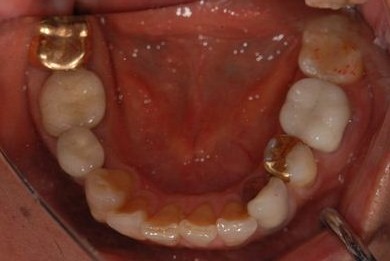

治療前

• 治療前

治療後

• 治療後